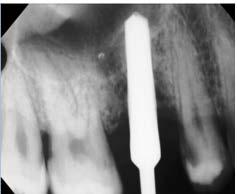

Figura 1. Ortopantomografía.

Figura 2. Radiografías periapicales de órganos dentarios con posibilidad de mantenerse en boca.

Figura 3. Fotografías intraorales.

hace 8 años por lo que toma 30 mg de nifedipino cada 12 horas, amlodipino 5 mg cada 24 horas, telmisartan 40 mg cada 12 horas y metropolol 100 mg cada 12 horas, además comenta padecer diabetes mellitus tipo II desde hace 7 años por lo que también toma 50 mg de metformina cada 12 horas y dapagliflozina 10 mg cada 24 horas. Clínicamente se observó una encía roja y sangrante, profundos sondeos, una notable hiperplasia gingival, depósitos de cálculo y movilidad dental grado III en todos los órganos dentarios a excepción del segundo premolar superior derecho al canino superior izquierdo, quienes presentaban una movilidad grado II. Radiográficamente se encontró una pérdida de inserción radiográfica avanzada generalizada

Figura 4. Raspado y alisado radicular de órganos dentarios con posibilidad de mantenerse en boca.

en la arcada inferior, y grupos molares de ambos cuadrantes superiores (Figura 1), los únicos órganos dentarios con posibilidad de preservación en boca a través de terapia periodontal se encontraron en el sector anterior de la arcada superior anteriormente mencionados con movilidad grado II

(Figura 2). Por lo que se diagnostica con periodontitis generalizada, estado IV, grado C (Figura 3).